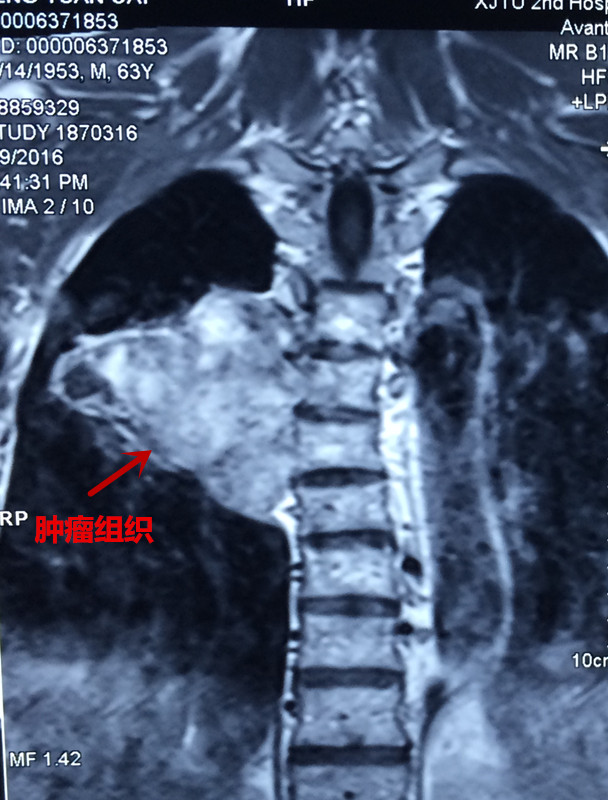

患者彭某,男,63岁,以胸背部疼痛5年,双下肢无力麻木半年之主诉入院,5年前无明显原因出现胸背部疼痛,影响夜休,就诊于当地医院,给与对症治疗,效果欠佳,背痛逐渐加重,长期服用非甾体类止痛药止痛,半年前无明显原因出现双下肢麻木、无力,走路不稳,进行性加重,未做治疗,2016年3月初就诊于当地医院,行胸椎MRI:胸6椎体水平椎管内外实质性暂未并胸6椎体附件、右侧第6肋骨骨质破坏,考虑恶性肿瘤可能,全身骨显像提示胸6椎体及右侧第6肋骨代谢异常活跃,恶性病变可能性大。当地医院拒绝治疗,为求进一步诊治,来我院门诊以“脊柱肿瘤”之诊断收入院。发病来食纳差,睡眠可,大小便正常,体重无明显变化。专科情况:脊柱生理弧度可,胸6棘突及附件压痛叩击痛阳性,半双下肢抽痛,双下肢肌张力可,肌力约3级,平乳头以下肢体感觉减退,无汗,双侧膝腱反射及跟腱反射阴性,双侧巴氏征阴性,左侧踝阵挛阳性。

患者入院后,王栋副主任,李锋涛主治医师高度重视,仔细询问患者病情,进行专科查体,分析以往患者的影像学资料,由于肿瘤组织生长巨大,严重压迫右肺,并且已经破坏了胸6椎体及其附件、右侧第6肋骨等,局部结构复杂,为了帮助手术方案的设计,我们采用3D打印技术,术前将肿瘤局部解剖结构打印成3D模型。邀请胸外科张维教授多次会诊,根据3D打印模型制定了详细的手术计划及围手术期治疗方案。经过严密的手术前准备,以王栋副主任、张维教授为主刀、李锋涛主治医师为助手,吴刚副主任医师、罗斌医师为麻醉医师,殷敏、马霞为配合护士,黄亚娟、王芳医师为术中诱发电位监护医师的手术团队努力下,手术顺利完成,成功切除了胸腔内、椎体旁及椎管内肿瘤组织,并进行了脊柱的重建。术后患者恢复良好,很快下肢感觉、肌力恢复,现患者正在康复中。